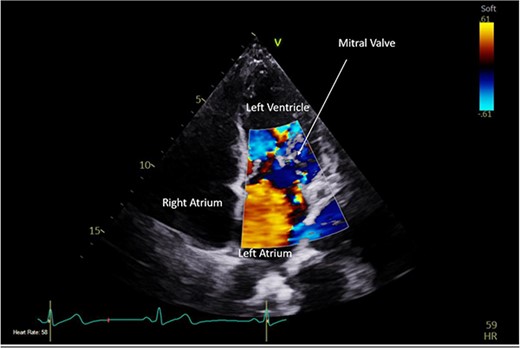

Pre-operative TTE with Doppler depicting mitral valve with vegetation (labelled).

Intra-operatively, femoral–femoral bypass was established and a 3 cm windsock vegetation was found with a 1.5 × 1.5 cm hole at the aortic inlet on the annular junction. The vegetation travelled from the LV to LA as shown in Figs 3 and 4. The vegetation was excised and the valve debrided, which resulted in moderate regurgitation from severe. Hence, a further 26 mm Physio II ring was placed resulting in no mitral regurgitation. The excised vegetation is shown in Fig. 5 and the post-op TTE images are shown in Figs 6 and 7.